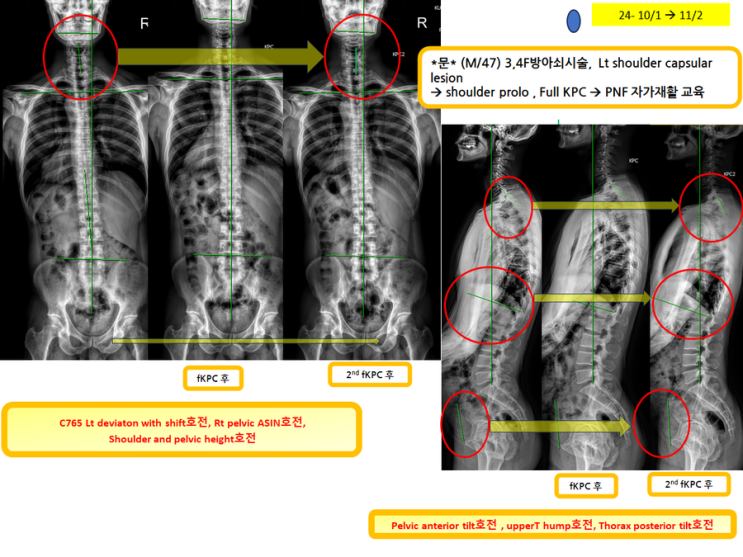

방아쇠시술하면서 full KPC후 2번째 full KPC하러 분!(녹는실KPC치료는 엑스레이 호전을 10분만에 확인)

방아쇠시술하면서 full KPC후 2번째 full KPC하러 분! (녹는실KPC치료는 엑스레이 호전을 10분만...